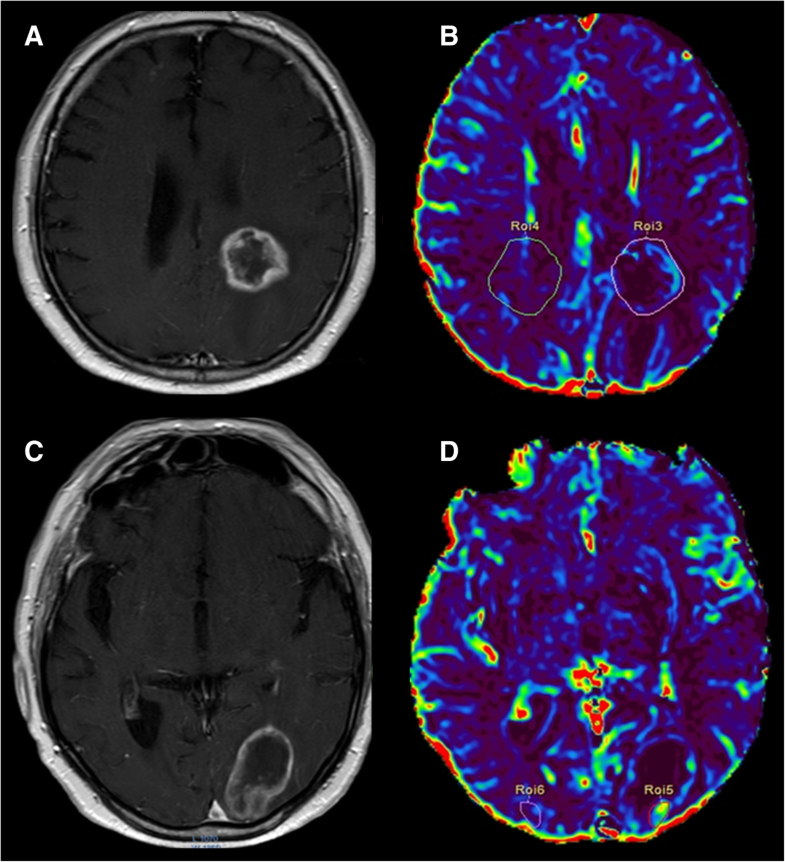

DCEMRI perfusion scans. In progression (top row), T1 contrast What Is A Mri Brain Perfusion Most of the impediments that have limited the use of per. A brain perfusion scan is a type of brain test that shows the amount of blood in certain areas of your brain. A brain perfusion scan is used to detect changes in the blood flow in the brain. Most of the impediments that have limited the use of. This. What Is A Mri Brain Perfusion.

DCE and DSC perfusion MRI diagnostic accuracy in the followup of What Is A Mri Brain Perfusion This can help show how your brain is. A brain perfusion scan is a type of brain test that shows the amount of blood in certain areas of your brain. Most of the impediments that have limited the use of per. Perfusion mri is a promising tool in assessing stroke, brain tumors, and neurodegenerative diseases. A brain perfusion scan is. What Is A Mri Brain Perfusion.